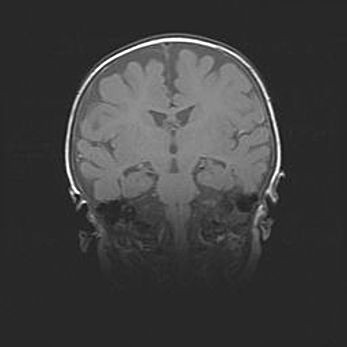

Множественные кисты обоих полушарий головного мозга, наибольшая из них в правой затылочной области. Ассиметричная атрофическая гидроцефалия.

Возраст: 7 месяцев

Вес: 5660 г

Пол: мужской

Окружность головы: 41,5 см

Срок гестации: 28-29 недель

Кисты головного мозга развиваются в результате многоочаговых некрозов вещества мозга и возникают вследствие перенесенной перинатальной инфекции, менингитов, энцефалитов, асфиксии, родовой травмы, расстройств мозгового кровообращения различного генеза. Образованию кист в веществе головного мозга плодов и новорожденных способствуют такие факторы, как высокое содержание в нем воды, недостаточная (или отсутствие) миелинизация и слабая астроглиальная реакция на повреждение.

Кисты могут сочетаться с гидроцефалией и другими поражениями головного мозга.